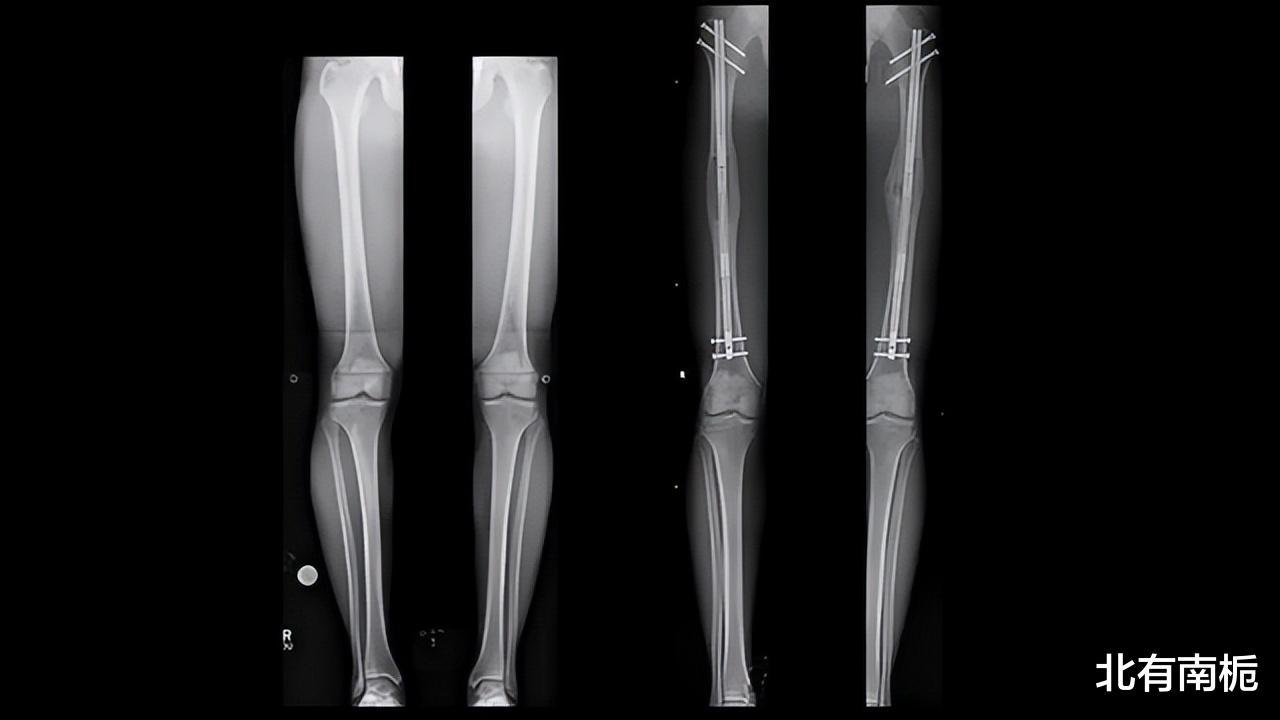

断骨增高手术前后变化

医生温柔仔细的回答道:“7.2厘米是患者骨骼承受最大的拉扯距离,如果再长的话会对患者的小腿、肌肉和骨头都有不同程度的损伤,而且同时也会增加患者术后复健的难度”。

医生首先在李亚诺的膝盖下方钻一个直径为3厘米的小洞,再将金属棒放入胫骨当中,以后金属棒也将成为他身体的一部分。

再接着在李亚诺两个小腿处插入大概10根固定针,做完这一切后再将双腿缝合,最后在双腿外侧带上金属固定器,这固定器也将陪伴他很长一段时间。

通俗易懂的解释就是将在膝盖下方的骨头打断,使得骨头骨骼线绽开,再在骨头中间移植一小节钢板,让钢板成为身体的一部分。

打断的骨头会连着钢板愈合,但这项手术风险很大,除了一些骨头畸形的患者几乎没有人愿意为此付出代价。